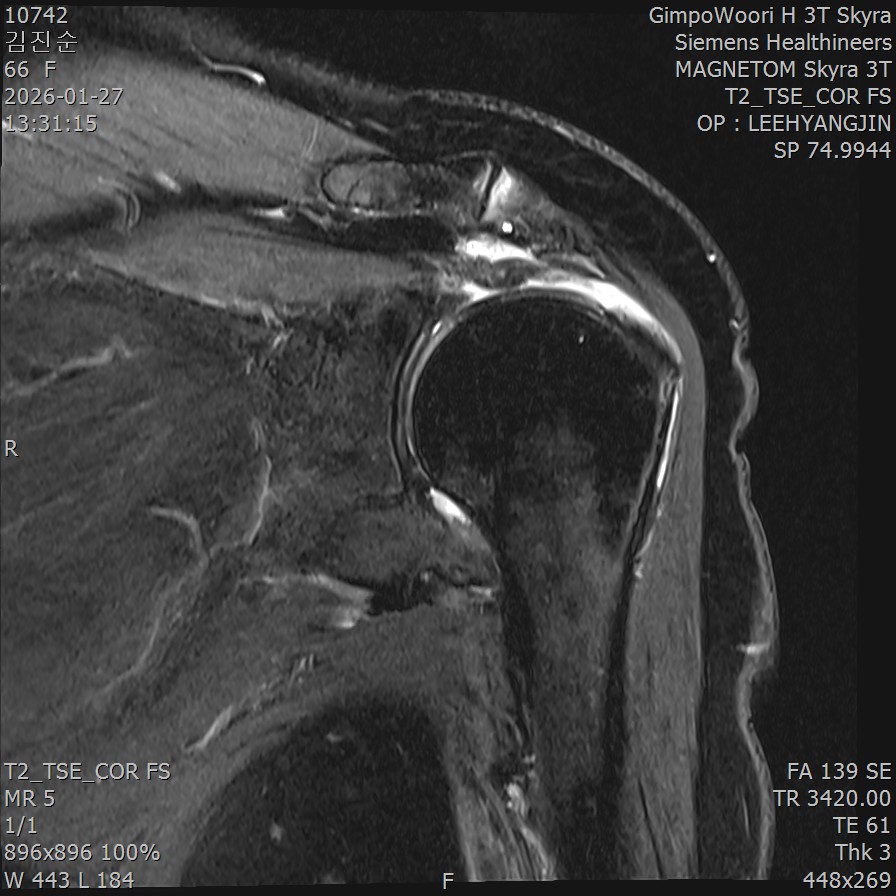

MRI 검사: 관절 내부까지 봅니다

- ✓회전근개 파열의 정확한 범위

- ✓완전파열 시 인대의 퇴축(말려 들어간) 정도

- ✓관절 내부의 문제 (관절와순 손상)

- ✓어깨 연골 상태

MRI의 한계: MRI는 환자가 가만히 누워서 팔을 움직이지 않은 상태에서 촬영합니다. 따라서 움직일 때만 발생하는 문제는 놓칠 수 있습니다.

MRI에서 이상이 없다고 했는데 통증이 지속되거나, 움직일 때만 통증이 발생하는 경우에는 둘 다 시행하는 것이 좋습니다.

Q9. MRI에서 정상이라고 했는데 왜 아픈 건가요?

A. MRI는 정지 상태에서 촬영하기 때문에, 움직일 때만 발생하는 문제는 놓칠 수 있습니다.